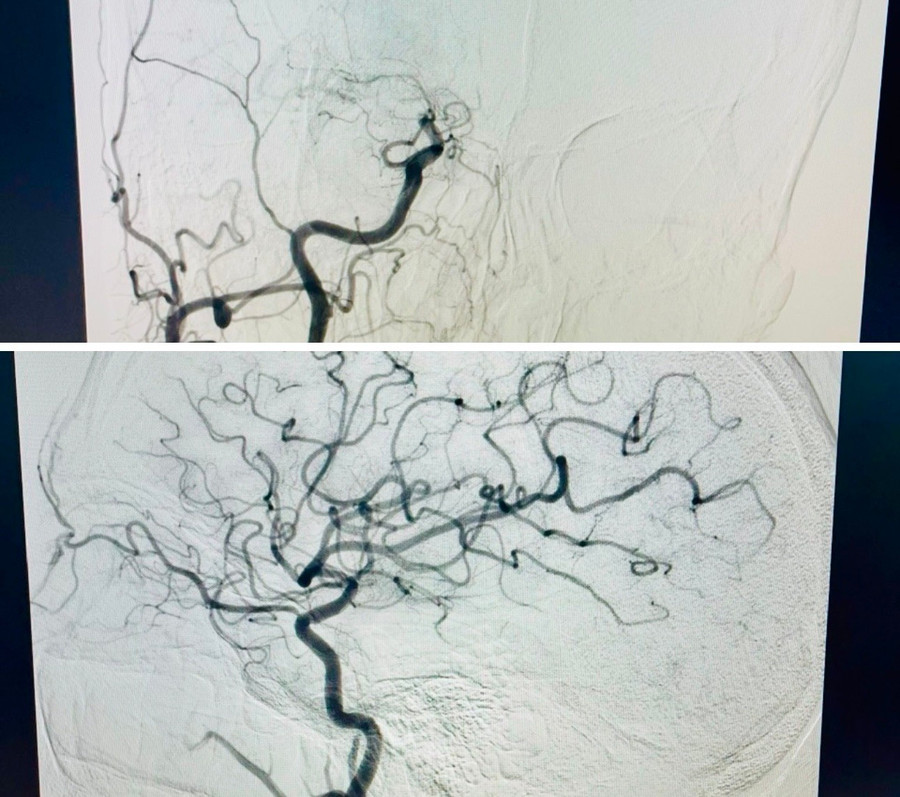

Hình ảnh chụp mạch trước và sau khi can thiệp của người bệnh. Ảnh: ĐVCC

Sau đó, bệnh nhân được chỉ định chụp cắt lớp vi tính mạch máu não, phát hiện tắc đoạn cuối động mạch cảnh trong - động mạch chính nuôi tuần hoàn trước của não - do cục huyết khối từ tim di chuyển lên gây tắc.

Ê kíp Đơn vị Đột quỵ đã nhanh chóng tiến hành chụp và can thiệp lấy huyết khối bằng hệ thống Chụp mạch số hóa xóa nền (DSA). Sau hơn 1 giờ can thiệp, cục huyết khối được lấy ra thành công, tái thông hoàn toàn mạch máu não.

Đến sáng 16-2, bệnh nhân gần như hồi phục hoàn toàn, sức cơ tay chân trái cải thiện lên 4/5, có thể tự ăn uống và sinh hoạt. Hình ảnh chụp cắt lớp vi tính kiểm tra cho thấy không có biến chứng sau can thiệp, Bệnh nhân tiếp tục được điều trị và dự phòng tái phát đột quỵ theo hướng dẫn Bộ Y tế.